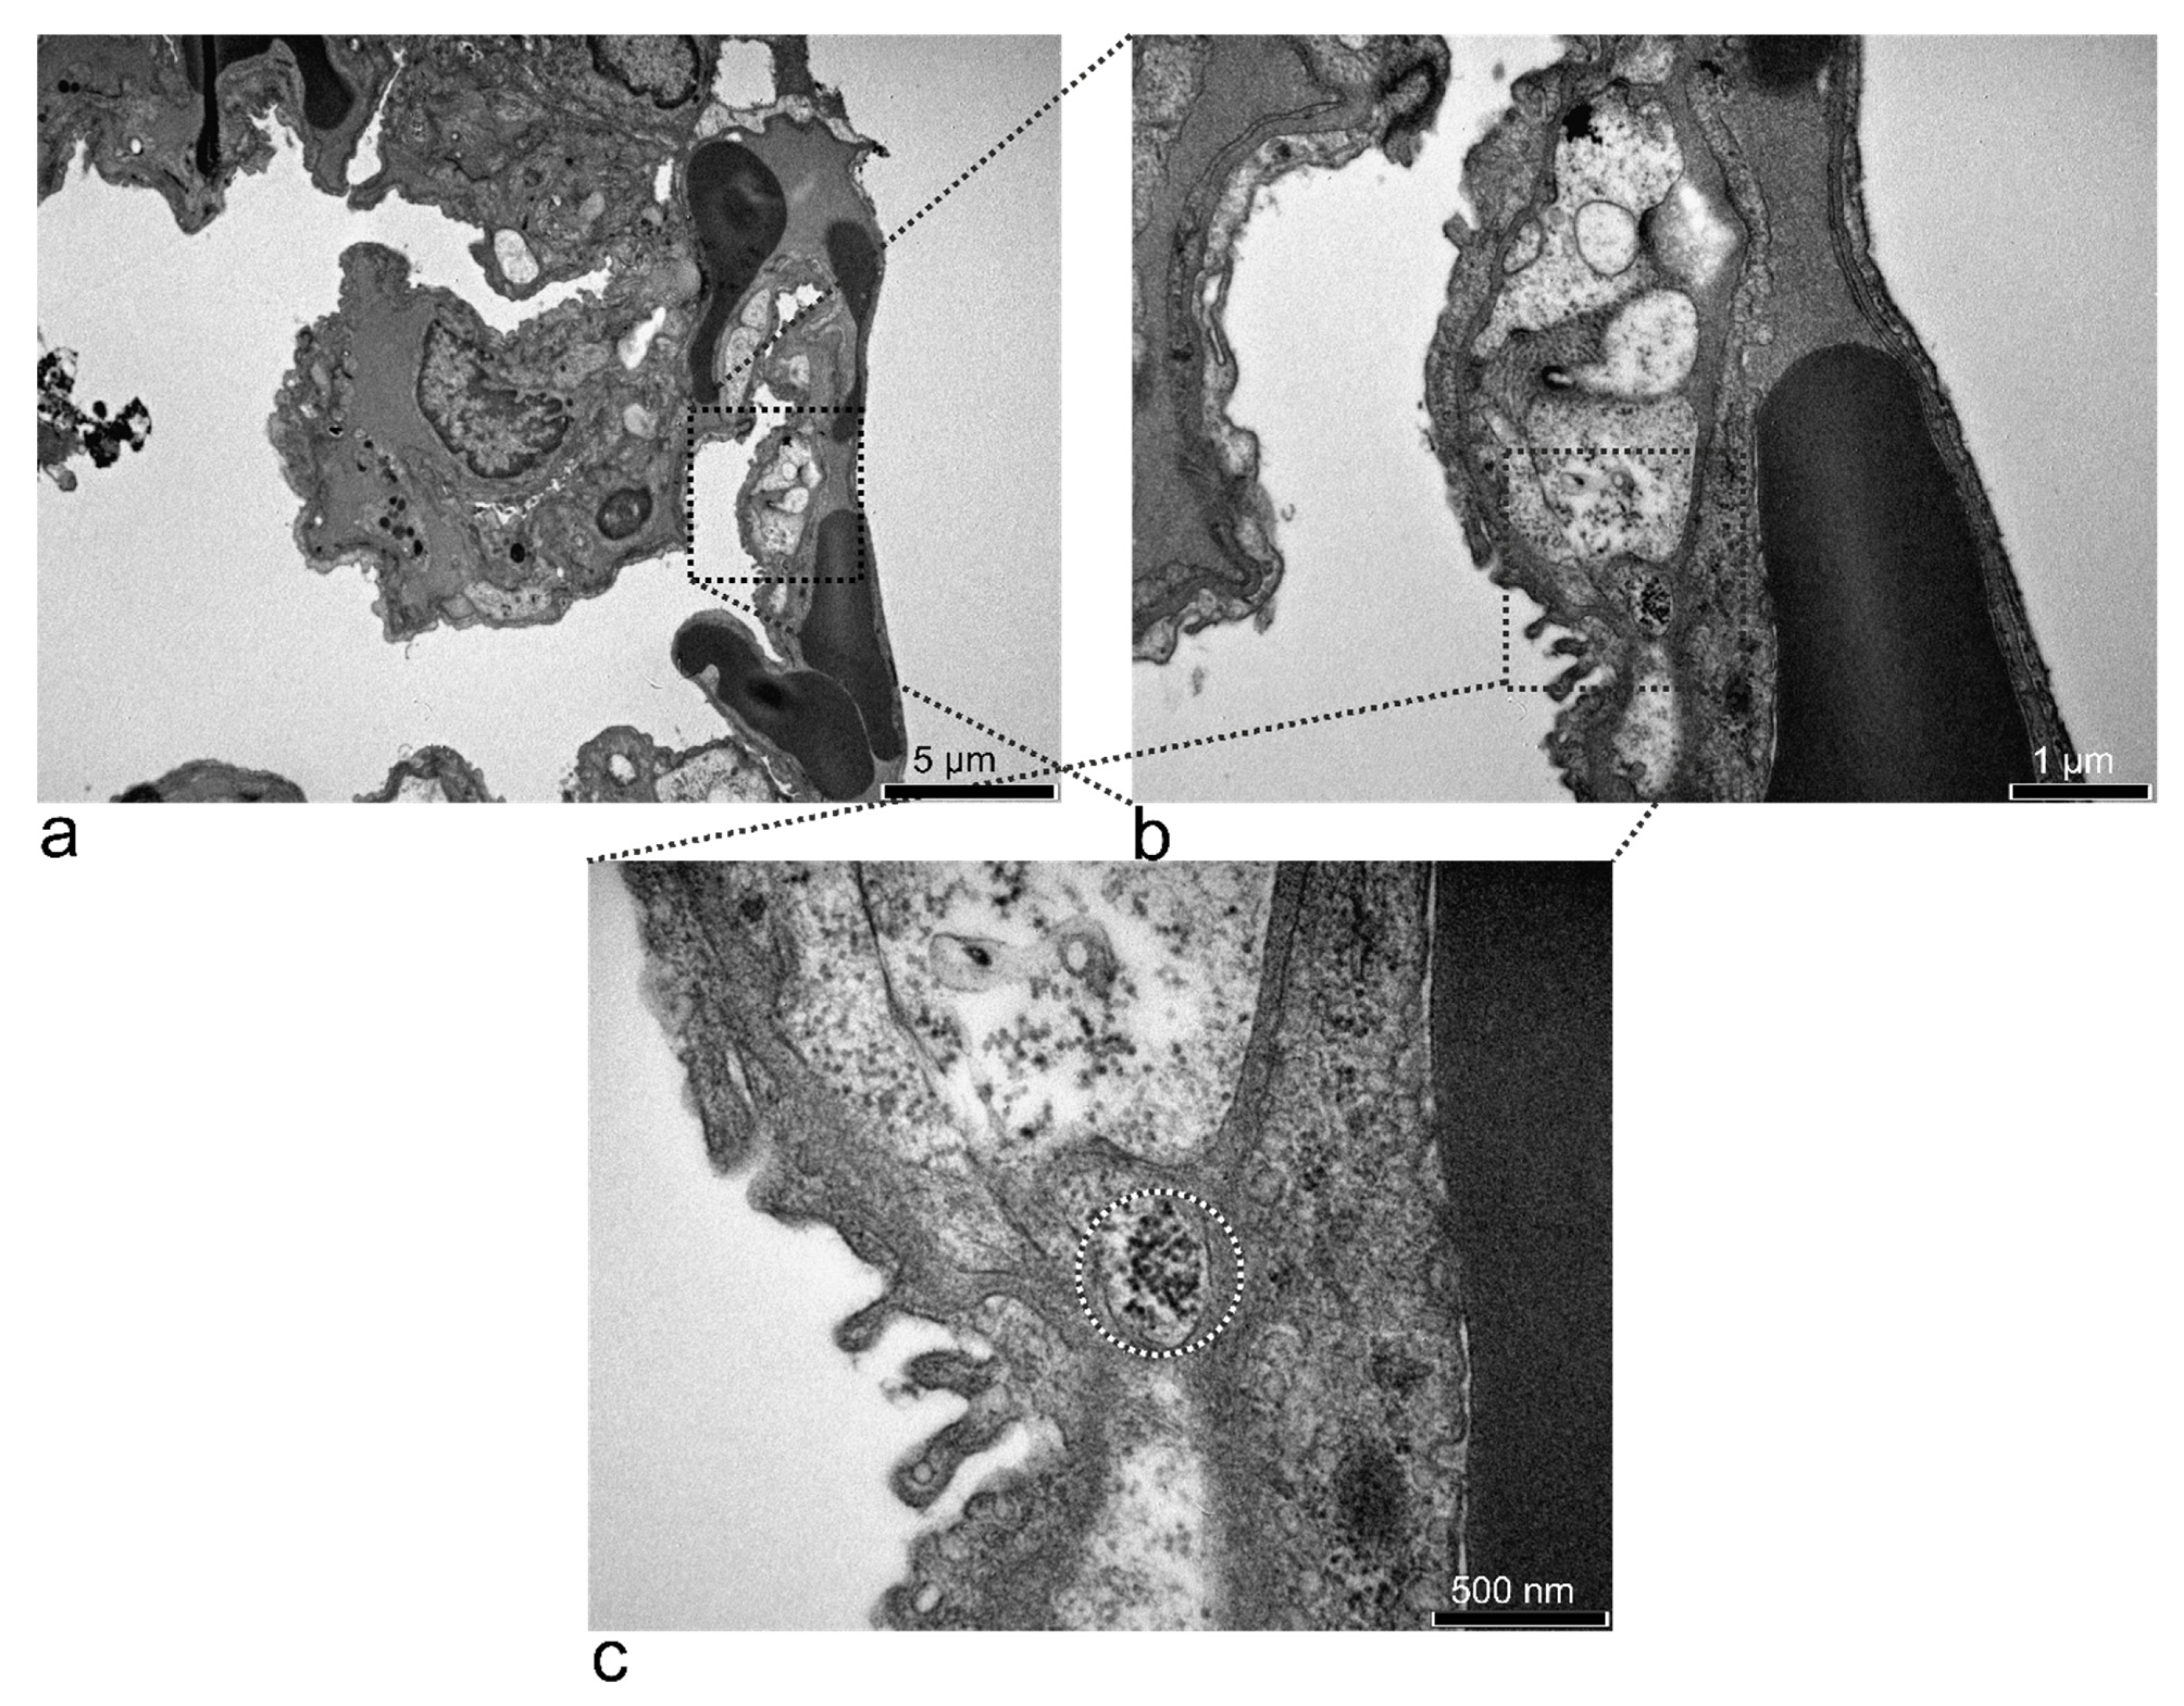

3.5.3. Kidney

| kidney | u.u. | n.p.m. | u.u. SPION in | n.p.m. | n.p.m. | n.p.m. | n.p.m. high number of electron-dense particles in the macrophages and parenchymal cells | n.p.m. high number of electron-dense particles in the macrophages and parenchymal cells |